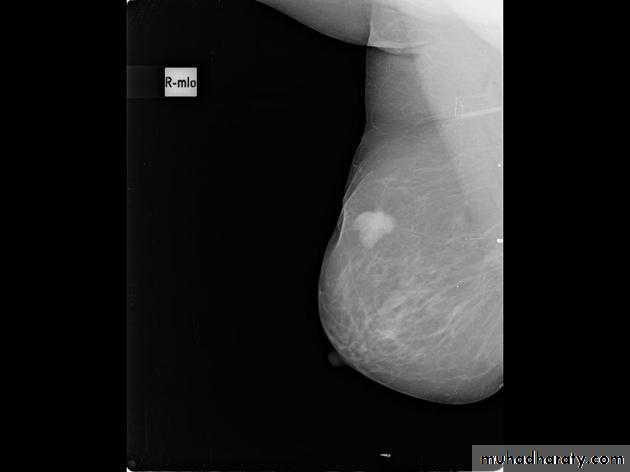

The mediolateral oblique (MLO) view is one of standard mammographic views. It is the most important projection as it allows to depict most breast tissue.

The sensitivity of mammography for the detection of ILC reportedly ranges between 55-80% 8. Because of the limitations of mammography in detecting ILC, other modalities, such as sonography and MR imaging, are being used in evaluating clinically suspicious findings and known cancers to assess the extent of disease. ILC are more commonly seen on the craniocaudal (CC), compared to the mediolateral oblique (MLO).